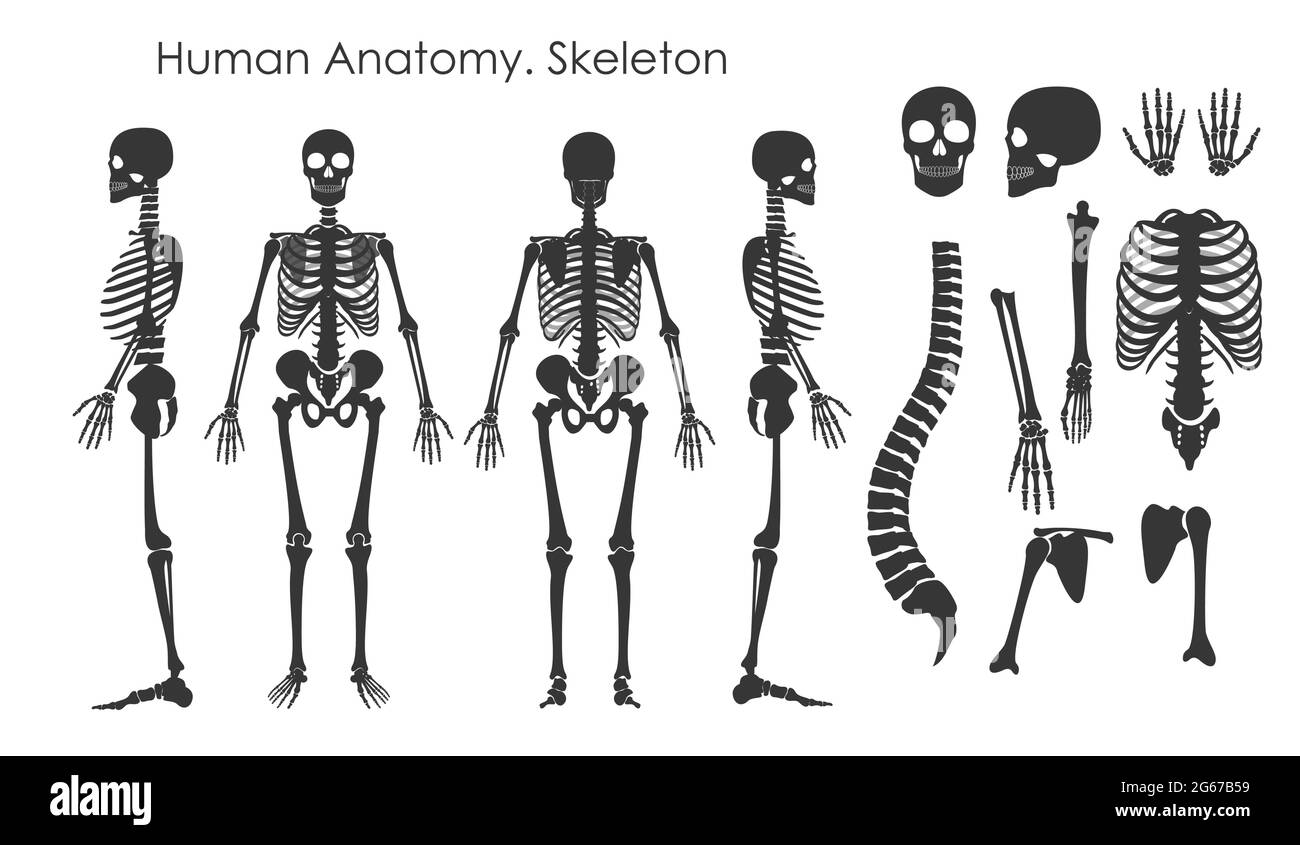

RF2G67B59–Ensemble d'illustrations vectorielles d'os humains squelette de style silhouette isolé sur fond blanc. Concept d'anatomie humaine, squelette dans différent

RF2G676H4–Ensemble d'illustrations vectorielles du squelette humain. Collection de silhouettes All Human Bones de style plat isolée sur fond blanc.

RF2AYYE9J–Os humains squelette silhouette vecteur. Ensemble d'os, de rachis illustré et d'os du crâne

RF2C6DFAE–Ensemble de collection silhouette squelette Human Bones. Illustration vectorielle haute précision

RF2C7550A–Ensemble de collection de silhouette de squelette d'or de luxe humain. Illustration vectorielle haute précision